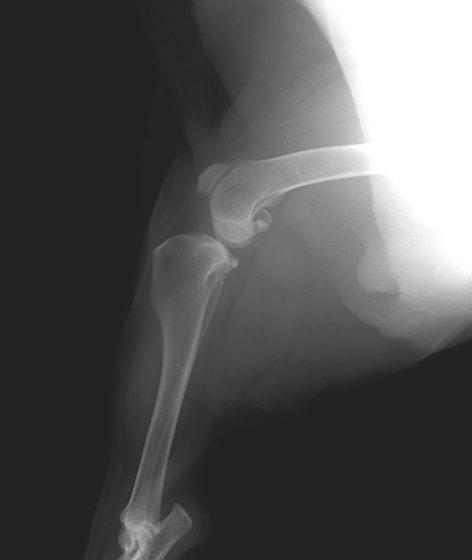

症例:右大腿骨遠位部の肉腫 クランバー・スパニエル 9歳 雌(未避妊)

2か月前から右後肢の完全挙上が認められ、消炎剤による内科治療で改善しないとのことで、他院から紹介来院した。

レントゲン検査

骨生検および病理組織検査

レントゲン検査所見から、骨もしくはその周囲組織に発生した腫瘍の可能性が考えられたため、病変部の細胞診検査およびジャムシディ生検針を用いた病変の骨生検を実施した。病理組織検査の結果、非上皮性の悪性腫瘍である“肉腫”と診断された。

内科治療に反応が乏しい四肢の跛行や疼痛は、本症例のように腫瘍が原因となっていることがあるため、レントゲン検査、骨生検等積極的に原因追及のための検査を実施することが必要である。骨の破壊を起こす悪性腫瘍は、非常に強い痛みを伴い、消炎鎮痛剤を用いても痛みを抑えることが困難となる。痛みの除去および腫瘍の治療のために断脚手術や抗がん剤等が必要となる場合があり、似た症状を示す整形外科疾患等とは治療法・予後が異なるため、その鑑別は重要である。